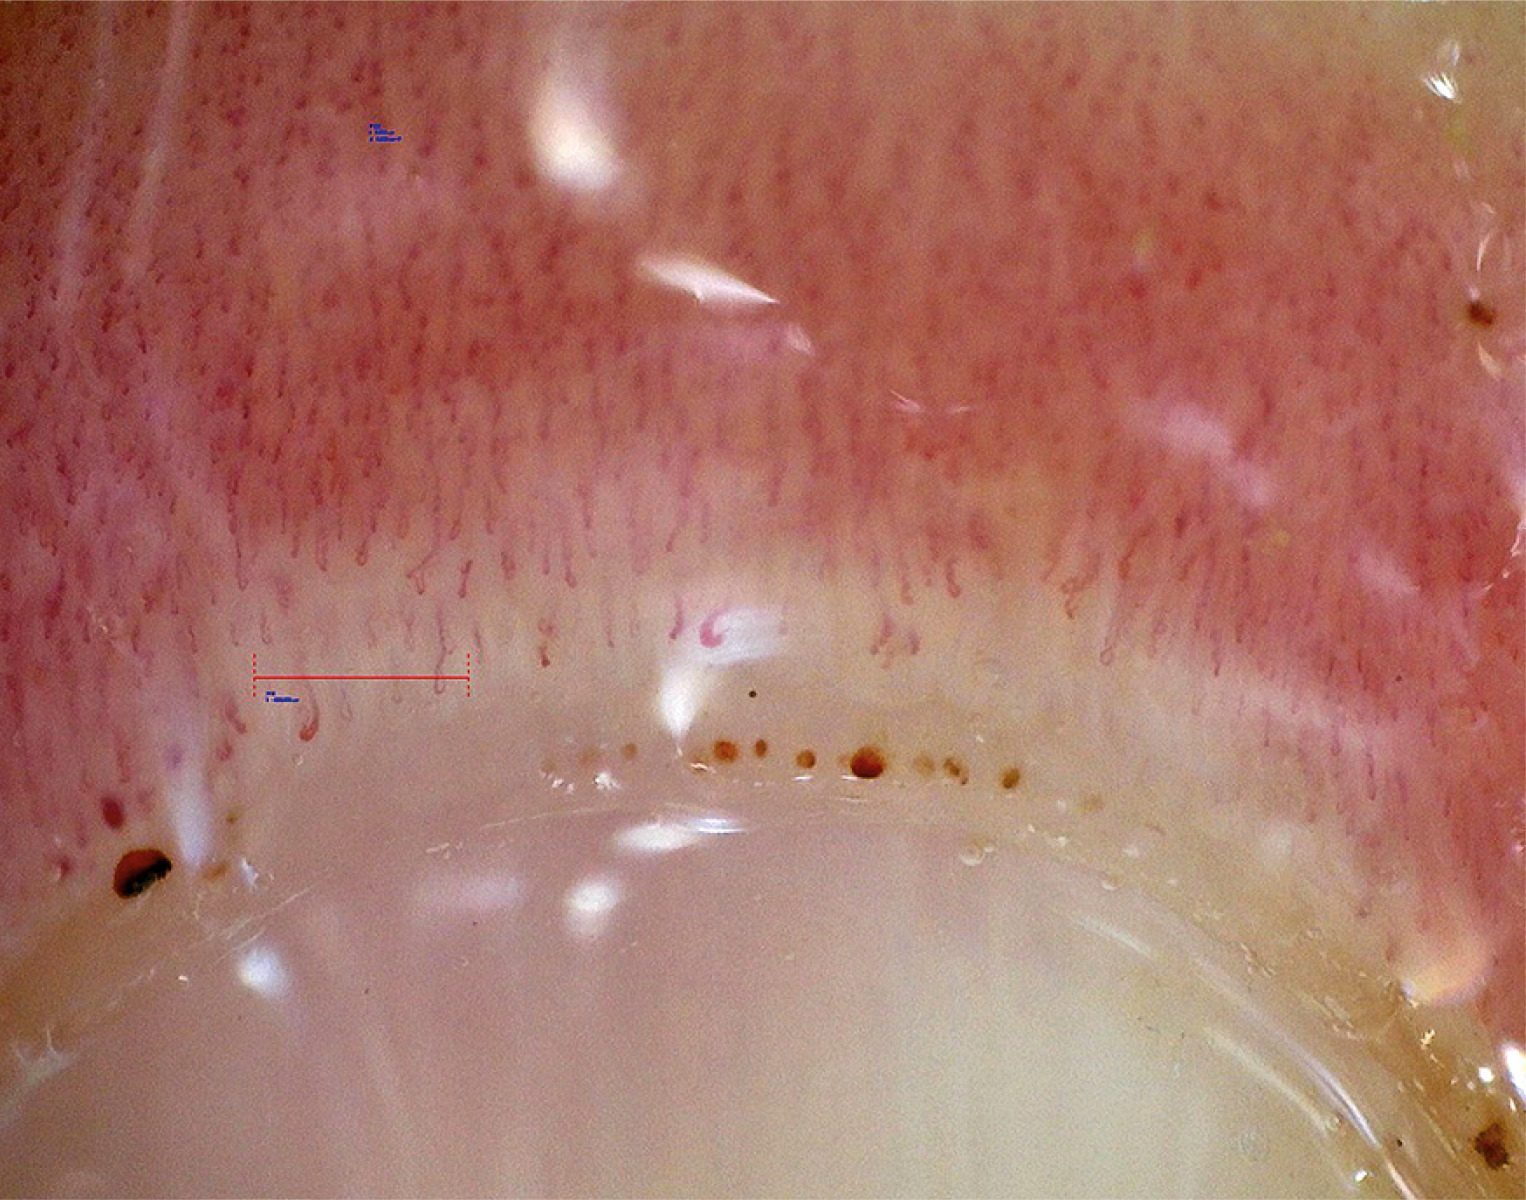

Capillaroscopic patterns in MCTD are very diverse, ranging from normal patterns, through nonspecific changes, to scleroderma-like patterns. Capillaroscopic changes in the form of scleroderma-like microangiopathy are found in about 50–60% of patients with MCTD (Fig. 2) [19]. In 1 comparative study, which examined patients with MCTD, SSc, and systemic lupus erythematosus (SLE), the “scleroderma-like” pattern was detected in 64% of patients with MCTD [19]. Interestingly, in a large prospective observational study lasting 4.8 years in a cohort of 3,029 patients with RP, a significant association was observed between the presence of a “scleroderma-like” pattern and the development of MCTD [20]. There are studies that have shown an association of scleroderma-like microangiopathy, especially the presence of giant vessels, with interstitial lung disease (ILD) and pulmonary arterial hypertension in patients with MCTD, and reduced capillary density correlated with a more severe course of this disease [21, 22]. Nevertheless, Ornowska et al. [23] described 2 cases of patients with MCTD and ILD. Both of them had a decrease in capillary density in nailfold capillaroscopy. However, in the first patient, the capillaroscopic image was connected with severe lung disease with coexisting pulmonary arterial hypertension. In the second case, the course of ILD was mild, which indicates that the decrease in capillary number was irrelevant. Therefore, these data require confirmation in a larger number of patients [23]. Generally, patients with MCTD, compared to patients with SSc, are characterized by a smaller degree of reduction in capillary density and fewer avascular areas in capillaroscopic examination [24]. In 1 study, during a 3-year follow-up, a lesser progression of capillaroscopic changes in MCTD was demonstrated, compared to SSc, in the form of less vessel reduction and a smaller number of giant vessels [25]. In another comparative study evaluating capillaroscopic findings in patients with MCTD and those with UCTD, a significantly higher frequency of the “scleroderma-like” pattern was demonstrated in patients with MCTD [22]. Despite the occurrence of various capillaroscopic changes in MCTD, identification of a specific capillaroscopic pattern in the course of this disease is impossible due to the coexistence of similar changes in other scleroderma spectrum diseases. Diagnostic and prognostic value may only be significant when other clinical and serological aspects of the disease are taken into account [26, 27].

Fig. 2

Scleroderma-like microangiopathy in the course of mixed connective tissue disease (200× magnification).

Source: Ewa Wielosz archive images.